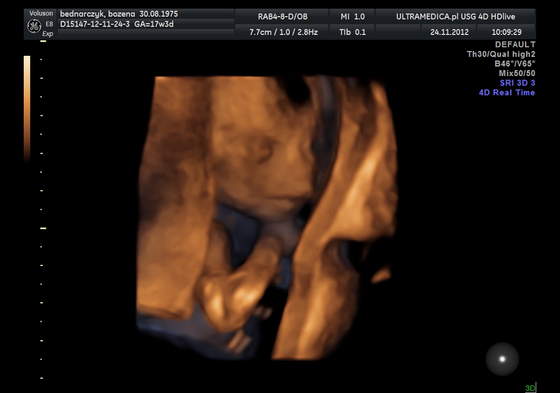

Też już jestem po wizycie i wszystko w porządku, dzieciaczek ruchliwy, a koniec machnął rączką, co mój M skomentował jako "siema"

Podobno wygląda na chłopca, ale to raczej zdecydowanie chyba za wcześnie. Niestety też nie mam zdjęcia, bo maszyna drukując odmówiła posłuszeństwa, ale to nic, następna wizyta przed świętami 19.12 i więc jest szansa